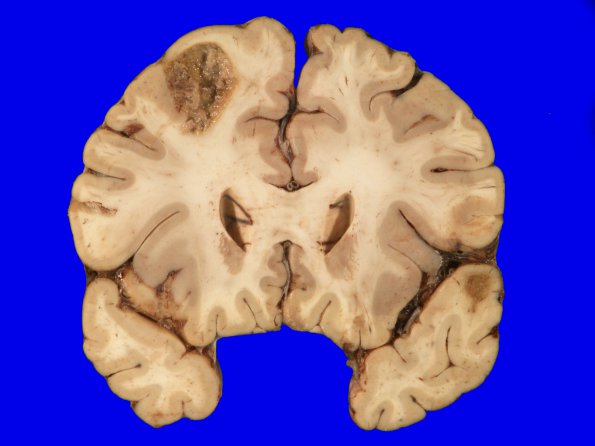

17A2 Metastasis, lung (Case 17) gross_3

Many of the tumor metastases are necrotic.